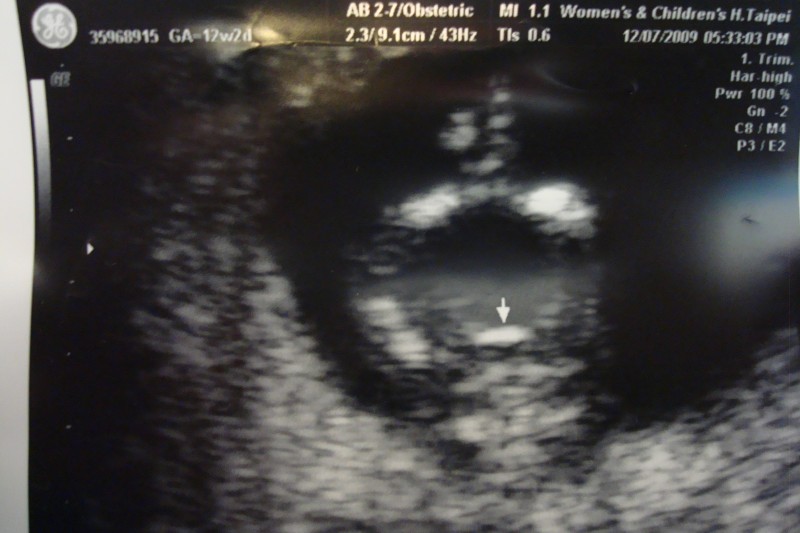

安定期 とよく聞かれます。 一般的に安定期と言われているのは、妊娠 12 週を超えた辺りから、です。 この時期を過ぎると流産が少なくなるとされているのが、その根拠の様です。 妊娠初期の流産は、そのほとんどが胎児側の原因、つまり、赤ちゃんに何らかの問題があり、成長できなかった事によって、流産になった、とされています。 つまり、成長でき12 週 0 12週から22週までの流産は後期流産といいます。 基礎体温が徐々に低温相に移動します。 多くの人はつわりの症状が軽くなります。 相対過敏期 妊 娠 4 ヶ 月 85 1 比較過敏期 85日から112日まで 催奇形性の影響は下がってきますが、妊娠12週で受検できる出生前診断 妊娠12週は、 妊娠初期から妊娠中期へと近づいていく時期 です。超音波検査のエコー写真では、胎児の見た目により人間らしさが出てきます。エコー検査のほかにも、出生前診断には多くの検査方法があります。

懷孕日記 12週自費產檢第一孕期妊娠風險評估 初唐 子癇前症風險評估 早產風險 禾馨懷寧 Lemopama 懷孕日記 小小蟻女的大大世界

助産師監修 妊娠12週目 妊娠4ヶ月 のお腹の中の赤ちゃんの様子について